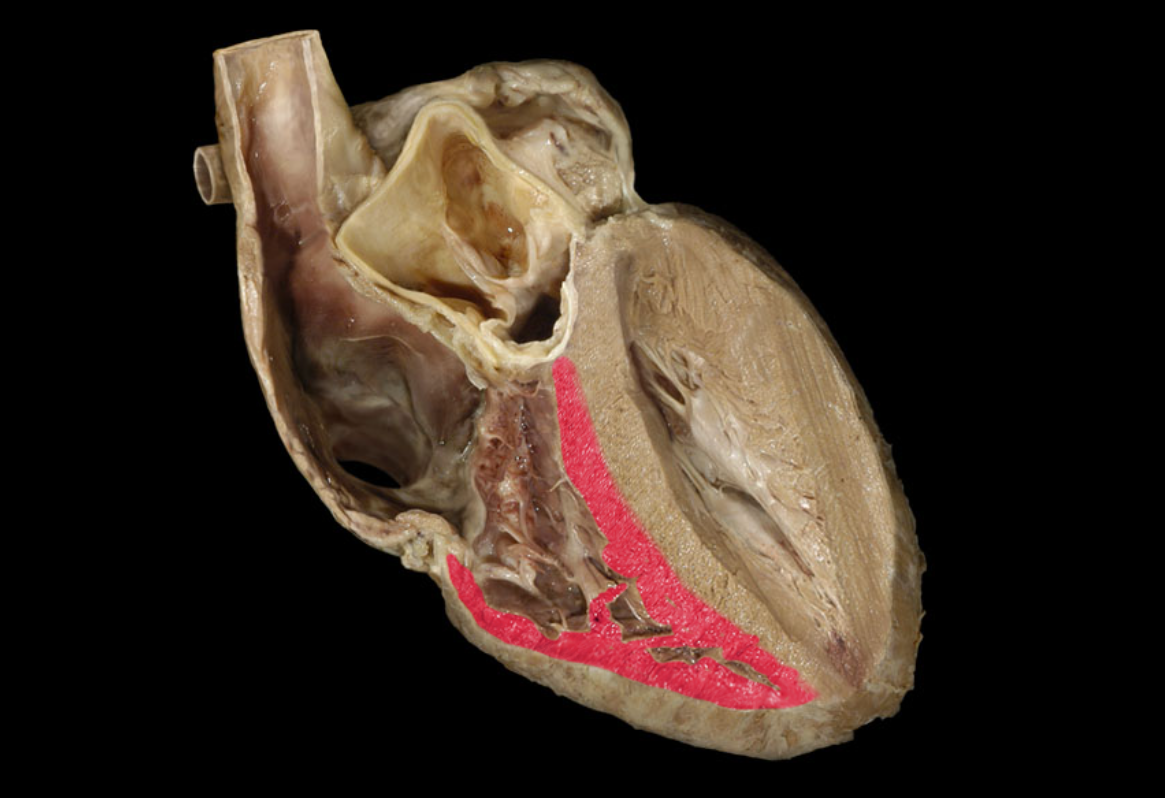

Blood from the superior and inferior vena cavae and the coronary sinus flow into the

right atrium

The tricuspid valve is located

between the right atrium and right ventricle

Contraction of the right ventricle leads to what action?

Closing of the tricuspid valve

How does the tricuspid valve close?

The contraction of the right ventricle forces blood against the cusps, which closes the valve.

What chamber of the heart pumps blood into the pulmonary trunk?

The right ventricle

Blood from the right ventricle flows to the_____ ______which then splits into two arteries (left and right) that lead into the lungs.

pulmonary, trunk

Which heart chamber receives blood that is low in oxygen?

The right atrium

Right atrioventricular valve

Right atrium

Right coronary a.

Right ventricle